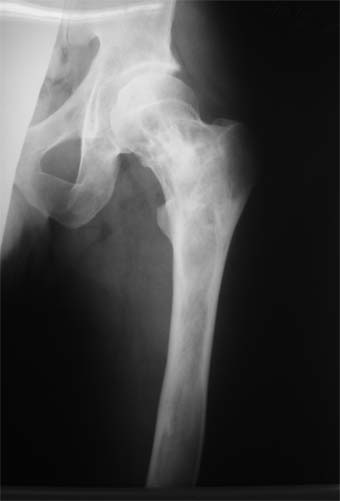

Коллеги!Пациент Д., 35 лет, В 1985 году был поставлен диагноз гемигипоплазия правой нижней конечности. Укорочение 5 см, в 1987 году остеотомия правого бедра, аппарат 4 месяца, удлинили на 2 см из-за нагноения спиц аппарат сняли. В настоящее время Жалобы на дискомфорт, тяжесть в левом бедре, голени при длительной ходьбе, при длительном лежании на левом бедре. Эти жалобы беспокоят втечение 5-6 лет. В 1999 году выявили "изменения" (со слов больного, выписки нет на руках) бедренной кости и костей голени слева. Тогда же предложили в ЦИТО срочно делать какую-то операцию. При осмотре: Правая нижняя конечность. Имеются рубцы на правом бедре по наружной и внутренней поверхностям. Ограничения движений в коленном суставе нет. Кровоснабжение, иннервация сохранены. Левая нижняя конечность. Левое бедро увеличено в объеме, при пальпации пальпируется бедренная кость большего диаметра по сравнению с левым бедром. Пальпация безболезненна. Голень обычной формы. Объем движений в суставах полный. Кровоснабжение, иннервация сохранены. Имеется разница в длине конечностей правая короче на 4-5 см за счет бедра и голени. В приложении вид больного и рентгенограммы бедра 2001 год и 2005 год. Что бы это могло быть? О чем можно думать? Онкология? С уважением Коробушкин Глеб Владимирович Российский государственный медицинский университет кафедра травматологии, ортопедии и ВПХ, доцент

У больного полиоссальноая форма фиброзной дисплазии с поражение левой бедренной и большеберцовой кости. На рентгенограммах - тотальное разрастание и остончение кортикального слоя. Имеется удлинение левой нижней конечности на 2,5-3 см за счет голени. Больному показано оперативное лечение левой большеберцовой кости.